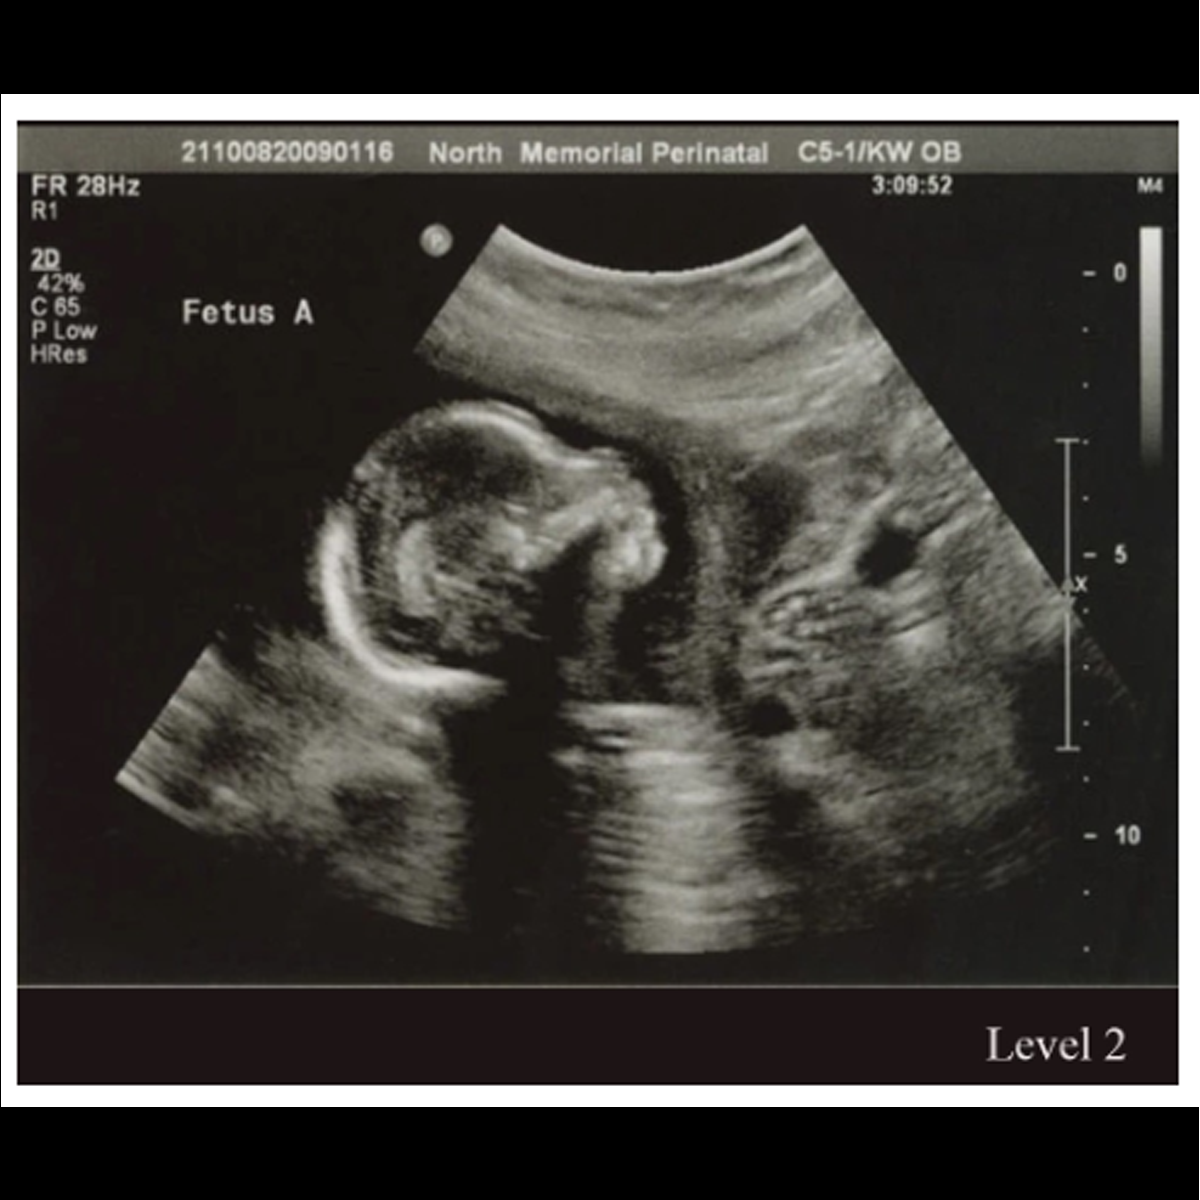

IV. Anomaly Scan / Level II (Done between 20-24 weeks):

Anomaly scan is done at 18-20 weeks of gestation to rule out major structural problems. Fetal growth, amniotic fluid are also checked at the same time. Some patients may need a review scan in case views are not clear due to maternal obesity, previous maternal surgery or at times due to fetal position. Indian MTP law doesn’t allow termination beyond 20 weeks even in case of major malformations and hence it is recommended to do anomaly scan before 20 weeks.